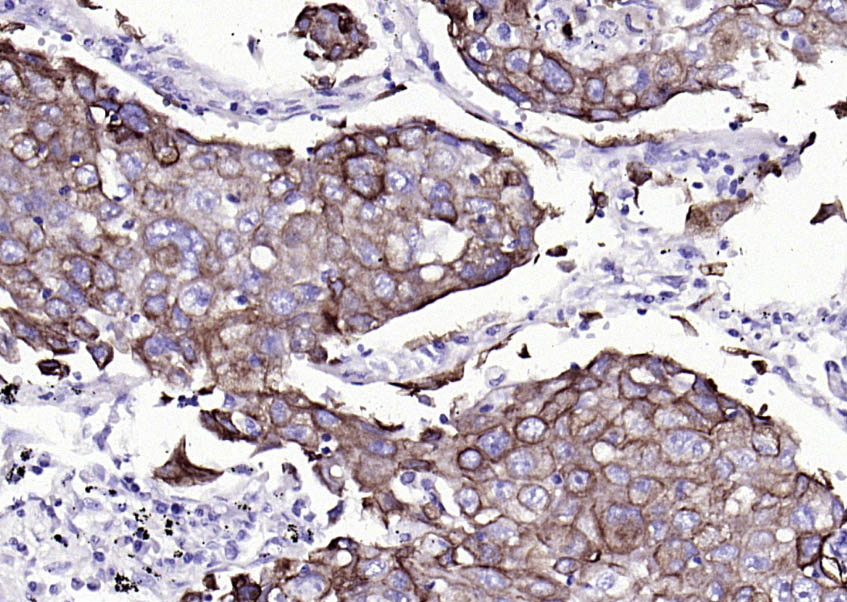

Vimentin is a developmentally regulated intermediate filament protein (IFP) found in cells of mesenchymal origin. It is believed to be involved with the intracellular transport of proteins between the nucleus and plasma membrane. Unlike other IFP proteins, vimentin is expressed, along with desmin, during the early stages of cellular development. During the development process, vimentin is exchanged for new, tissue-specific IFPs. Vimentin has been implicated to be involved in the rate of steroid synthesis via its role as a storage network for steroidogenic cholesterol containing lipid droplets. Vimentin phosphorylation by a protein kinase causes the breakdown of intermediate filaments and activation of an ATP and myosin light chain dependent contractile event. This results in cytoskeletal changes that facilitate the interaction of the lipid droplets within mitochondria, and subsequent transport of cholesterol to the organelles leading to an increase in steroid synthesis.

| IHC-P | Human, Mouse, Rat | 1:100-500 | |